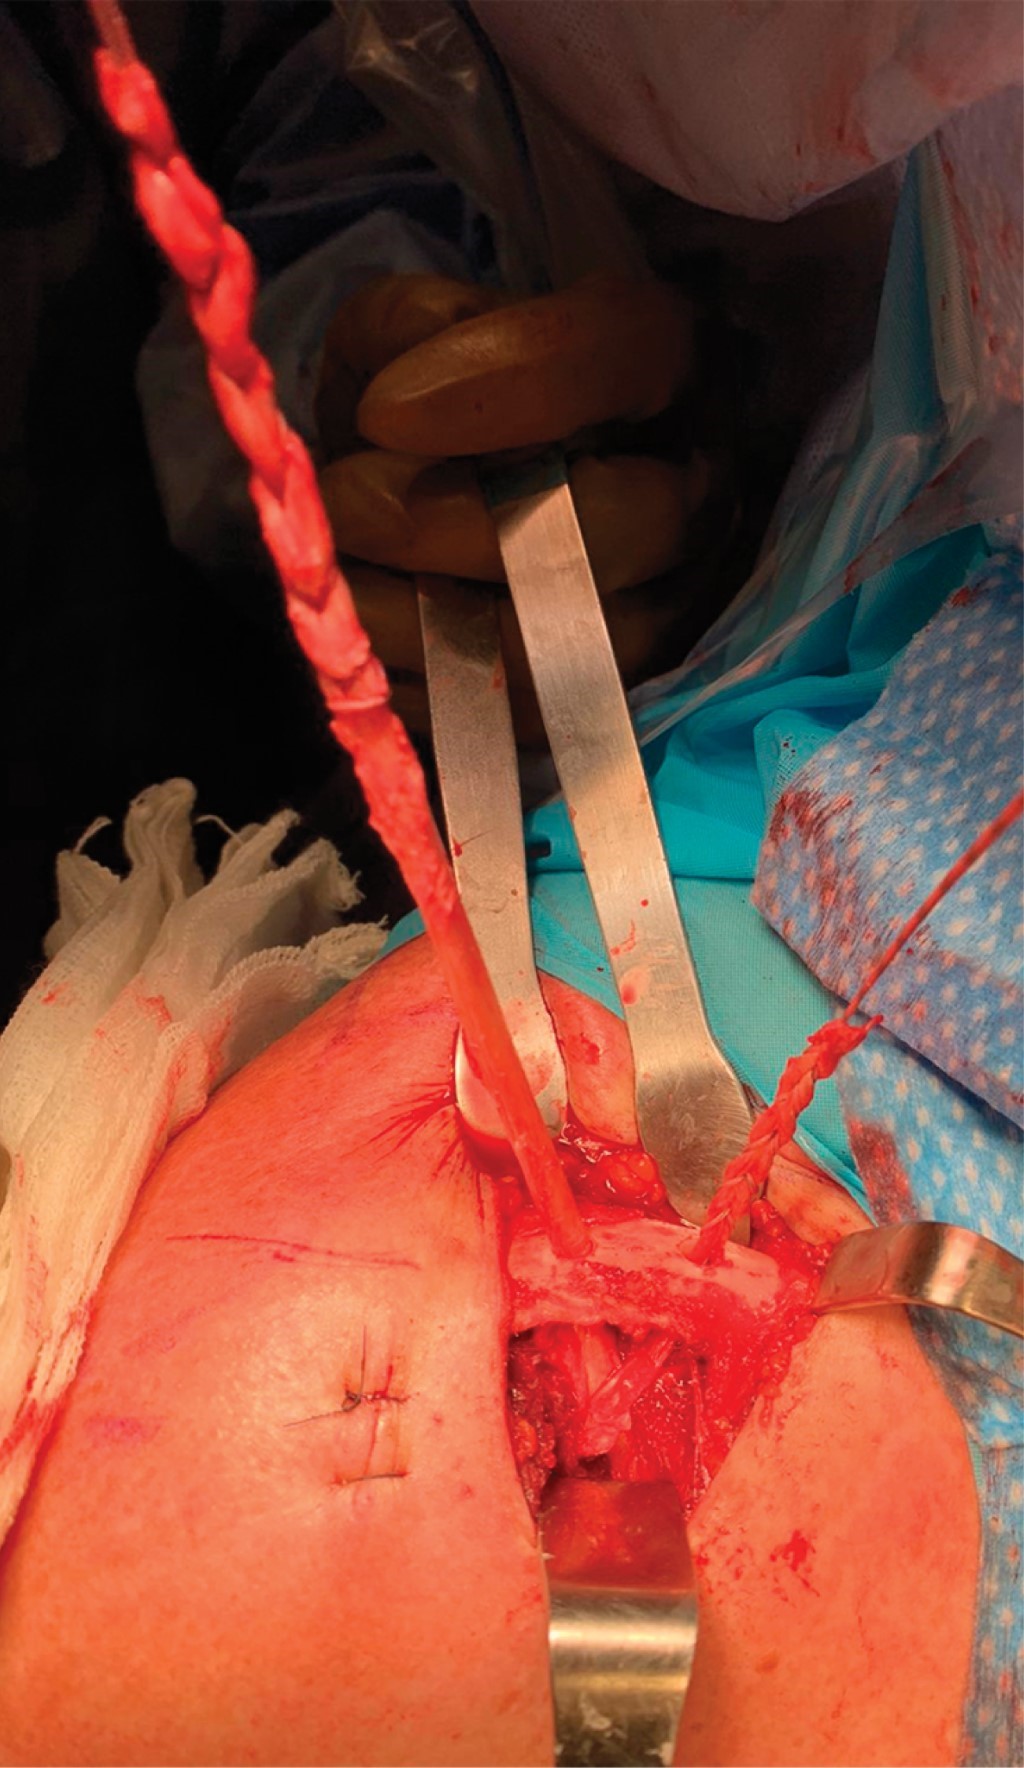

El injerto se pasa por debajo de la apófisis coracoides de medial a lateral bajo visión directa con ayuda de una guía de nitinol o de una gasa y se le da una configuración de "8" para pasar a través de ambos túneles en la clavícula (Figura 6).

Se hace una incisión de 3 a 2 cm distal del borde lateral del acromion, por donde se pasa guía de nitinol por debajo del acromion. Se efectúa reducción manual de articulación AC, mientras un ayudante realiza fijación de injerto en los orificios de la clavícula con dos tornillos de biotenodesis 5 × 15 mm observando una adecuada fijación del injerto y restableciendo la estabilidad vertical (Figura 7). Posteriormente, el remanente de cabo distal del injerto se pasa por debajo del acromion con ayuda de la guía de nitinol en la incisión lateral y se sutura con su cabo proximal en el borde superior de la clavícula con una sutura no absorbible (Figuras 8 y 9).

Figura 6

Figura 7